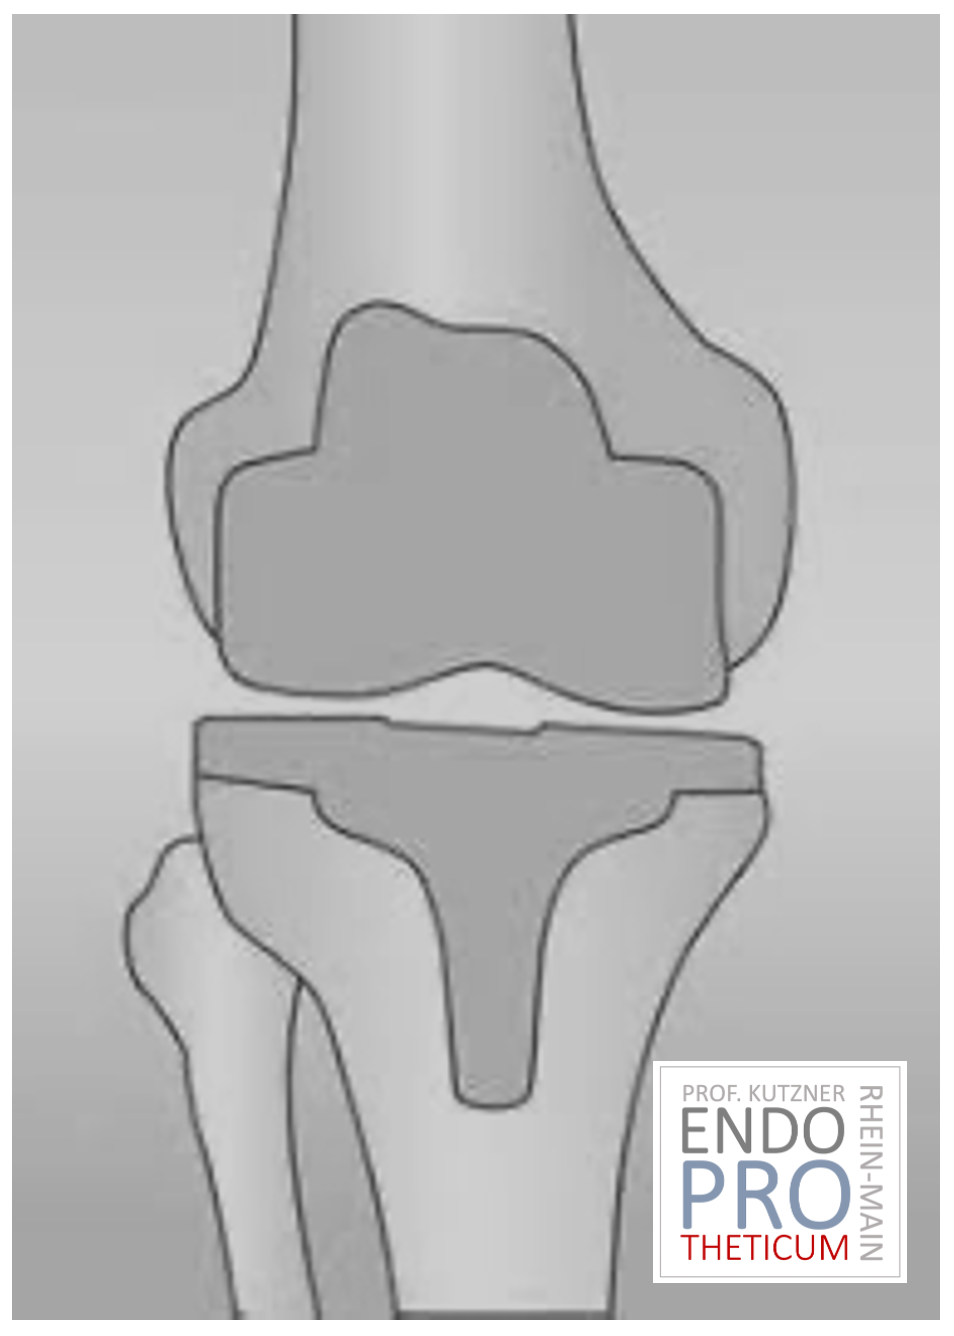

KNEE REPLACEMENT (ARTIFICIAL KNEE JOINT)

The artificial knee joint replaces the cartilage surface destroyed by arthrosis. The underlying bone on the thigh and tibial head remains intact. Some people compare a modern artificial knee joint to a crown on a tooth; the exact term is the so-called bicondylar surface replacement. Between the new surfaces on the thigh and lower leg is the so-called inlay made of a specially hardened white plastic, which can be seen in the X-ray image as the gap between the metal parts.